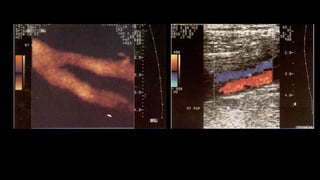

Doppler de miembrosinferiores en la insuficiencia venosa 5 VSM VFC Figura 8 Corte longitudinal a nivel del ostium, donde se debe hacer la medición del diámetro de la VSM. - Se debe mencionar y evaluar la existencia de venas vari- cosas que no tengan relación con las safenas, así como también hay que establecer cuál es su procedencia (por ejemplo: vena pélvica), ya que la ligadura de las safenas puede no ser necesaria16 . En síntesis, el objetivo del examen es determinar el punto de fuga, la presencia de venas epifasciales insuficientes y el punto de reentrada, indicando la existencia de perforantes insuficientes y su localización. Parámetros a evaluar en el paciente safenectomizado con tratamiento de termo obliteración 1) Buscar si se evidencian tramos de safena e informar dónde comienzan y terminan. 2) Es importante tener en cuenta que en la etapa posquirúr- gica inmediata se pueden ver imágenes hiperecogénicas en la luz de la vena, habitualmente secundarias al tra- tamiento de termo obliteración con láser. Esto no debe ser confundido con trombosis y tiene que ser informado como safena termo-obliterada. ARTICLE+Model RARD-60; No. of Pages 8 6 Vena perforante Vena perforante insuficiente HD P T R 12,03,0 P T R 12,03,0 Figura 10 Vena perforante mayor de 3 mm con reflujo en el

reverso ante lasmaniobras de Valsalva en la unión safena- femoral (viraje de color rojo, en descanso a color azul, en Valsalva). +0,86 m/s –0,864 s m/s –0,11 +0,11 Vena femoral VSM Figura 5 Imagen que demuestra el cierre valvular correcto sin reflujo en la VSM con el Doppler color y espectral. Figura 7 Insuficiencia de la VSM en el tercio medio del m ante las maniobras de Valsalva. - Para examinar el eje de la VSP, con el paciente de e das al operador, se realizan cortes transversales en la posterior de la pantorrilla (de caudal a cefálico), vis zando la vena safena parva y calculando el reflujo e distintos niveles. Debe consignarse si es o no tortuo a qué altura desemboca en la vena poplítea (si es lo hace)15 , midiendo la distancia desde la planta del A su vez, hay que evaluar la presencia o no de la safena parva del muslo y, en caso de que esté prese definir si esta es suficiente o insuficiente. - A nivel del hueco poplíteo se busca la existencia de re en la vena poplítea. - Si se descubre insuficiencia de la VSP, también debe indicar si el ostium está involucrado o si el reflujo se i más caudalmente, si hay presencia de venas epifasc dilatadas y los puntos de reentrada del flujo. - Es necesario explorar las venas tibiales posteriores, a riores y peroneas. ARTICLE IN PRESSRARD-60; No. of Pages 8 4 H. Berardi, A. Ciccioli VSM Izquierda + ,07 – ,07 m/s +55,90 –54,98 cm/s 2 1 0 Vena femoral VSM 5,3s Figura 3 Doppler espectral con corte transversal evidencia una VSM suficiente ante las maniobras de Valsalva. HD 20 10 0 10 20 T R 12,03,0 P VSM HD Figura 6 Corte transversal de la VSM que muestra un aumento de las velocidades anterógradas (por encima de la línea de base), ante las maniobras de Valsalva.

INCOMPETENCIA  VENOSA vVenas incompetentesmuestran cambios de color, flujo retro y anterógrado con o sin maniobras compresivas. vDefectos de repleción debido a restos de trombos y depósitos de fibrina